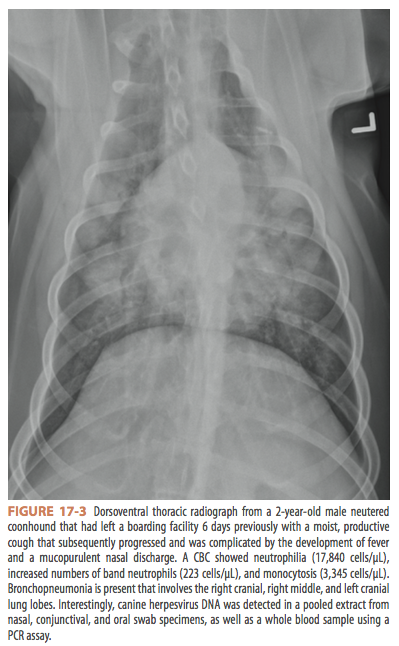

Canine Viral Respiratory Infections